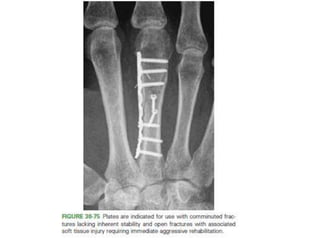

Open Reduction and Internal Fixation

• Indications :

– Intra-articular fractures that cannot be reduced

– multiple fractures without inherent stability

– open fractures especially when associated with tendon

disruptions.

• Internal fixation can be accomplished with

– intraosseous wiring,

– composite wiring,

– screws only, or

– Screws and plates